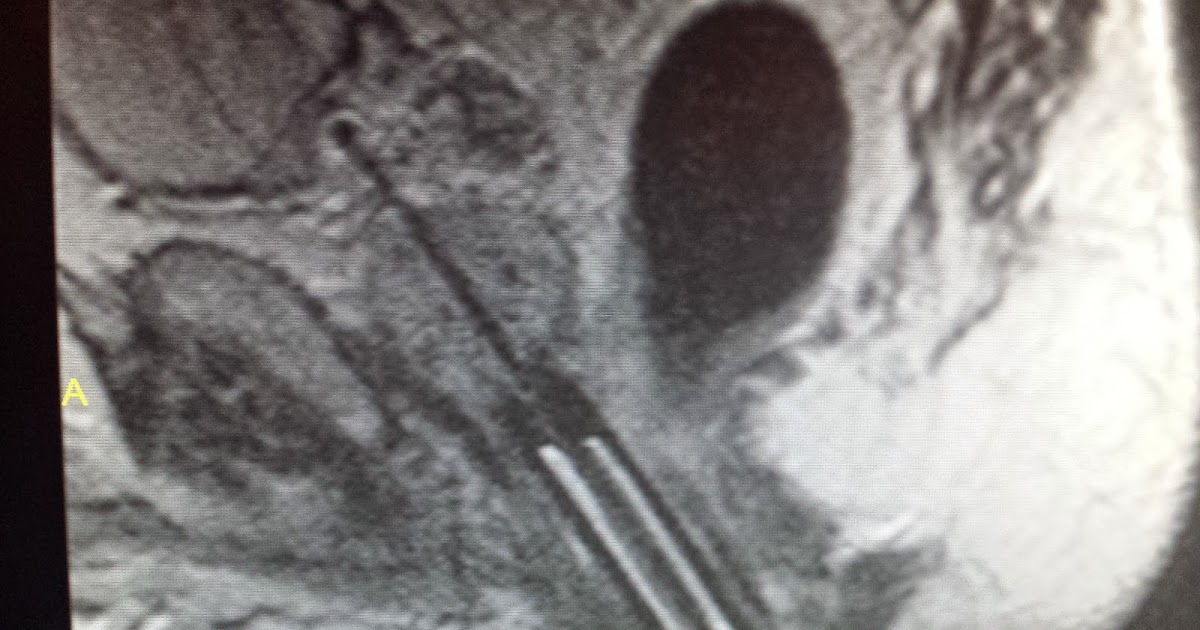

Click here to read our latest blog post on medicare reimbursement. The foundation is seeking more information about prostate cancer treatment being granted insurance coverage. This procedure is not covered by medicare or by any major insurance carriers, mri focal laser ablation can be considered for very small discrete tumors in the prostate that are well visualized by mri. At ucla, we are studying laser focal ablation. Prostate tissue is well suited for focal laser ablation due to its optical absorption rate without excess vascularity, which allows for finely controlled ablation. When properly selected, focal laser ablation produces the results that patients want without the side effects of surgery and radiation.

This procedure involves placing the patient inside the mri scanner and displaying mri. Laser focal therapy can also be used to help improve the symptoms associated with benign prostatic hyperplasia (bph). The laser treatment would be performed by dr. The cryoablation treatment is covered by my insurance company, but the laser treatment is not. Instead of putting it in the entire prostate, you actually choose the area with disease and put it only there.

This procedure involves placing the patient inside the mri scanner and displaying mri. There is now focal laser ablation which scott has been doing for a long time. Are focal laser ablations ation covered by insurance? When properly selected, focal laser ablation produces the results that patients want without the side effects of surgery and radiation. Medicare hmo blue sm and medicare ppo blue sm members medical necessity criteria and coding guidance for medicare advantage members living in

All methods, except focal laser ablation, use ultrasound guidance to focus on the tumor (focal laser ablation uses magnetic resonance imaging to guide the probe). The cryoablation treatment is covered by my insurance company, but the laser treatment is not. Participant eligibility includes age, gender, type and stage of disease, and previous treatments or health concerns. In some cases, private insurance will cover a large portion of the procedure, without copays or deductibles, for bph treatment. As with all new treatments, the problem is complex.

All methods, except focal laser ablation, use ultrasound guidance to focus on the tumor (focal laser ablation uses magnetic resonance imaging to guide the probe). At ucla, we are studying laser focal ablation. There are a narrow set of patients who are good candidates for focal laser ablation. Click here to read our latest blog post on medicare reimbursement. The advanced diagnostic protocols in use at the.